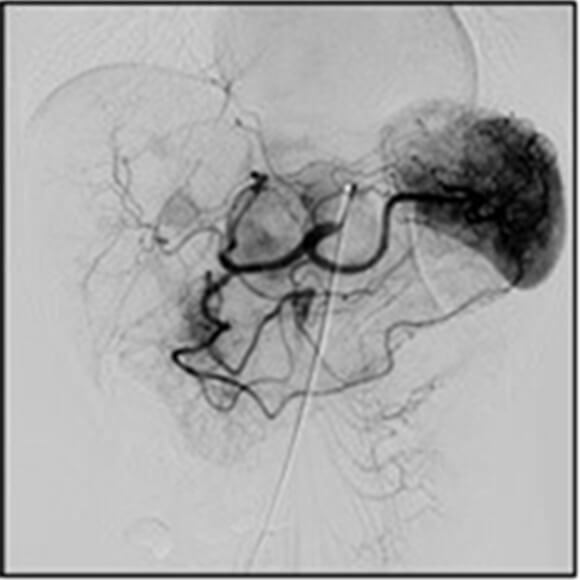

アンギオ検査部⾨

アンギオ検査とは⾜の付け根・⼿⾸・肘などからカテーテルと呼ばれる細い管を⾎管内に挿⼊し、造影剤を注⼊しながら⾎管のX線撮影を⾏う検査です。これにより⾎管の閉塞・狭窄やがんなどの臓器疾患の診断が可能となります。

近年、アンギオ検査は⾎管造影撮影による画像診断だけでなく、引き続き治療を⾏うIVR(InterVentional Radiology)が盛んに⾏われています。

治療部位に応じて⼿技はさまざまであり、⼼臓や四肢の狭くなったり詰まったりした⾎管にはバルーンと呼ばれる⾵船のついた管やステントと呼ばれる⾦属製の筒を挿⼊、または⾎管を拡張させるような薬を流すことで正常な状態に戻したり、症状を抑えるような治療を⾏います。がん疾患については、腫瘍を栄養している⾎管までカテーテルを進め、抗がん剤や塞栓物質を⽤い腫瘍を弱らせ、縮⼩させる動脈化学塞栓術を⾏います。その他、動脈瘤や外傷等による出⾎部位の⽌⾎については、コイルと呼ばれる塞栓物質により⾎管を詰まらせる⾎管塞栓術を⾏います。

当センターでは、⾎管内治療だけでなくX線透視下で⾏う検査及び治療についてはアンギオ装置を有効に活⽤できる体制を整備しております。

腹部⾎管

-

頭部⾎管

頭部⾎管

写真 キヤノンメディカルシステムズ株式会社提供